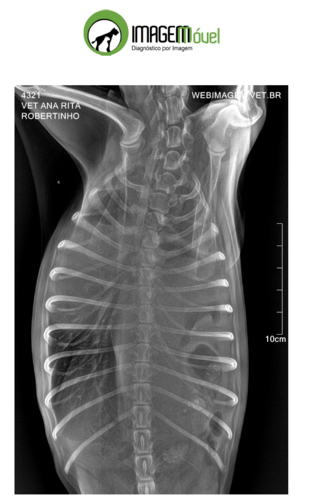

Pois bem, fazem algumas semanas que estamos notando que nosso amiguinho não está bem, então foi chamado uma veterinário que através de um exame de raio x constatou a urgência de cirurgia para nosso companheiro. Esses primeiros gastos já foram custeados pelos grupo de professores. Mas Robertinho provavelmente sofreu um trauma que ocasionou uma hérnia que está pressionando seu pulmão. Desse modo sem a cirurgia nosso amigo não irá sobreviver muito tempo.